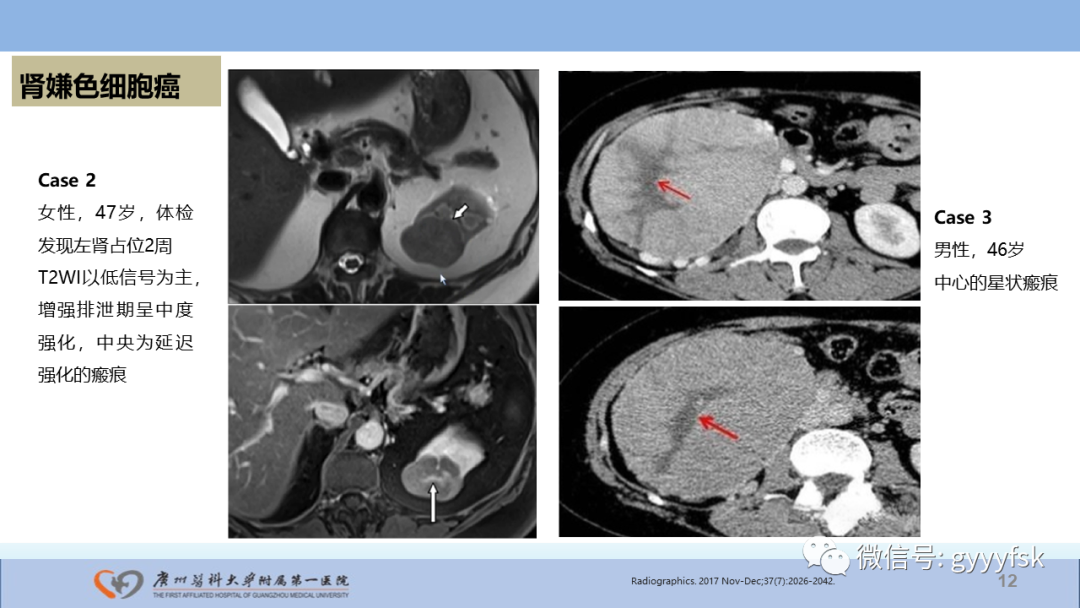

【PPT】肾癌相关影像诊断的文献汇报-12